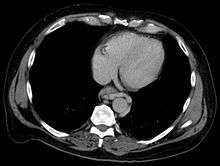

In medicine (gastroenterology), esophageal varices (or oesophageal varices) are extremely dilated sub-mucosal veins in the lower third[1] of the esophagus. They are most often a consequence of portal hypertension, commonly due to cirrhosis; patients with esophageal varices have a strong tendency to develop bleeding.

In situations where portal pressures increase, such as with cirrhosis, there is dilation of veins in the anastomosis, leading to esophageal varices. Splenic vein thrombosis is a rare condition that causes esophageal varices without a raised portal pressure. Splenectomy can cure the variceal bleeding due to splenic vein thrombosis.

Varices can also form in other areas of the body, including the stomach (gastric varices), duodenum (duodenal varices), and rectum (rectal varices). Treatment of these types of varices may differ. In some cases, schistosomiasis also leads to esophageal varices.